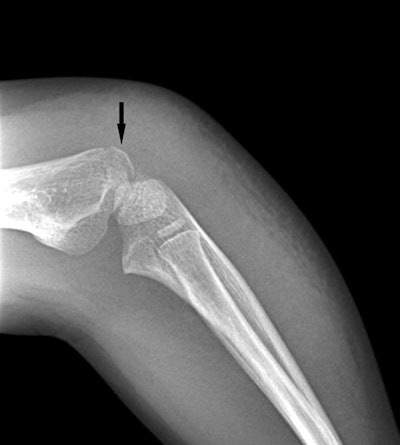

Radiology departments are facing a conundrum from the growing number of urgent care centers sending them x-rays that may not be of optimal diagnostic quality. A department in Texas offers some tips for improving urgent care pediatric imaging in research published online February 2 in the Journal of the American College of Radiology.

Researchers from Texas Children's Hospital in Houston found that there were subtle -- but statistically significant -- differences in image quality between urgent care images that were acquired with a registered radiologic technologist (RT) present and those where an attending general physician supervised the process. While it's not always economically feasible to have an RT onsite at a pediatric urgent care center, it doesn't mean radiology departments should give up on helping these sites improve their image quality, wrote a group led by Dr. J. Herman Kan.

"We have to keep in mind that we're exposing children to radiation, so it's imperative to get diagnostic quality images," Kan told AuntMinnie.com.

Kan and colleagues sought to assess x-ray quality at pediatric urgent care centers with and without radiologic technologists. The group compared 235 radiographic exams performed at four pediatric urgent care centers without a technologist and 83 exams performed at two centers with a technologist.

The researchers evaluated the studies for quality using a five-point scale (1 = poor, 5 = best), assessing field-of-view, presentation, and orthogonal view orientation, as well as incidence of positive results, the need for repeat imaging, and discrepancies between initial imaging and follow-up exams. The average daily number of x-ray exams taken at facilities with dedicated technologists was 1.36, and the average number taken at facilities without dedicated technologists was 0.96.

The incidence of repeat imaging, discrepancy rates between initial imaging and follow-up, and the incidence of abnormal radiographic findings did not differ significantly between the two groups. But the researchers did find significant differences between them for field-of-view, presentation, and orthogonal view orientation -- in favor of exams performed by technologists.